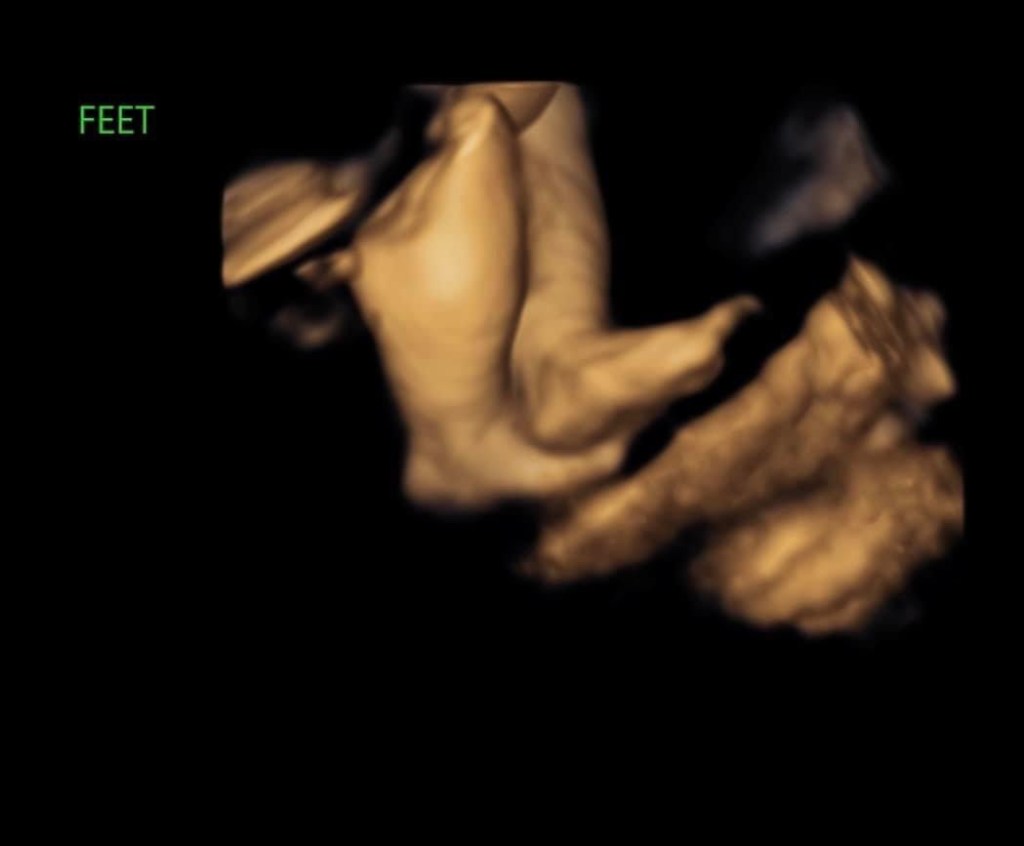

Amelia lived 38 weeks, 5 days in my womb and she lived 11 days after she was born. We are forever changed for having known and loved her.